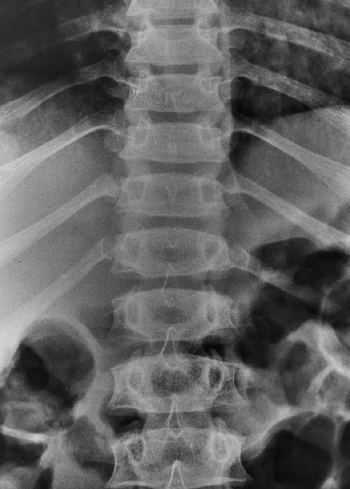

early childhood, but never quite reach normal (28). The spine displays central and foraminal stenosis, which becomes worse at progressively caudal levels (30,31).

Although stenosis may occur at any level, it is most common in the

lumbar spine; this is evident on plain films as a constant or

diminishing distance between pedicles, from the first to the fifth

lumbar levels on the anteroposterior view (Fig. 8.5),

Figure 8.5

This anteroposterior view of the entire spine shows the progressive narrowing of the interpedicular distance at more caudal levels of the lumbar spine; this is the opposite of the normal pattern. |